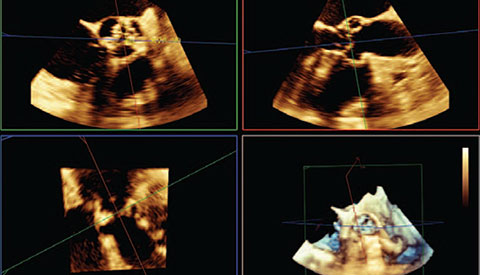

Uw patiënt is gediagnosticeerd met symptomatische aortastenose. Ze is 85 jaar, heeft diabetes en een hoge bloeddruk. U weet dat ze een verhoogd risico loopt en niet in aanmerking komt voor hartchirurgie, maar misschien wel voor transkatheter aortaklepvervanging (TAVR). Vandaag de dag bieden innovatieve beeldvormingsoplossingen en percutane instrumenten hoop voor sommige patiënten die tot nu toe geen andere opties hadden .